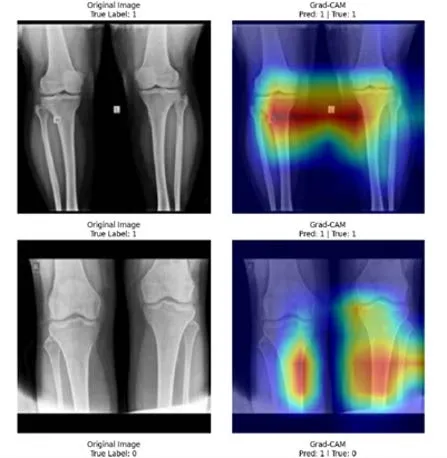

這門醫工實驗-醫學資訊課程在電腦教室上機進行,透過實作方式讓逐步熟悉 MATLAB 的基本語法與操作流程。從矩陣運算、資料讀寫、視覺化,到機器學習與深度學習模型,課程內容循序漸進,讓我了解醫學資訊分析的實際應用情境。實驗操作有助於培養程式撰寫與數據分析能力,也加強我對跨領域整合與終身學習重要性的認知,對未來修習進階醫工或研究課程相當有幫助。